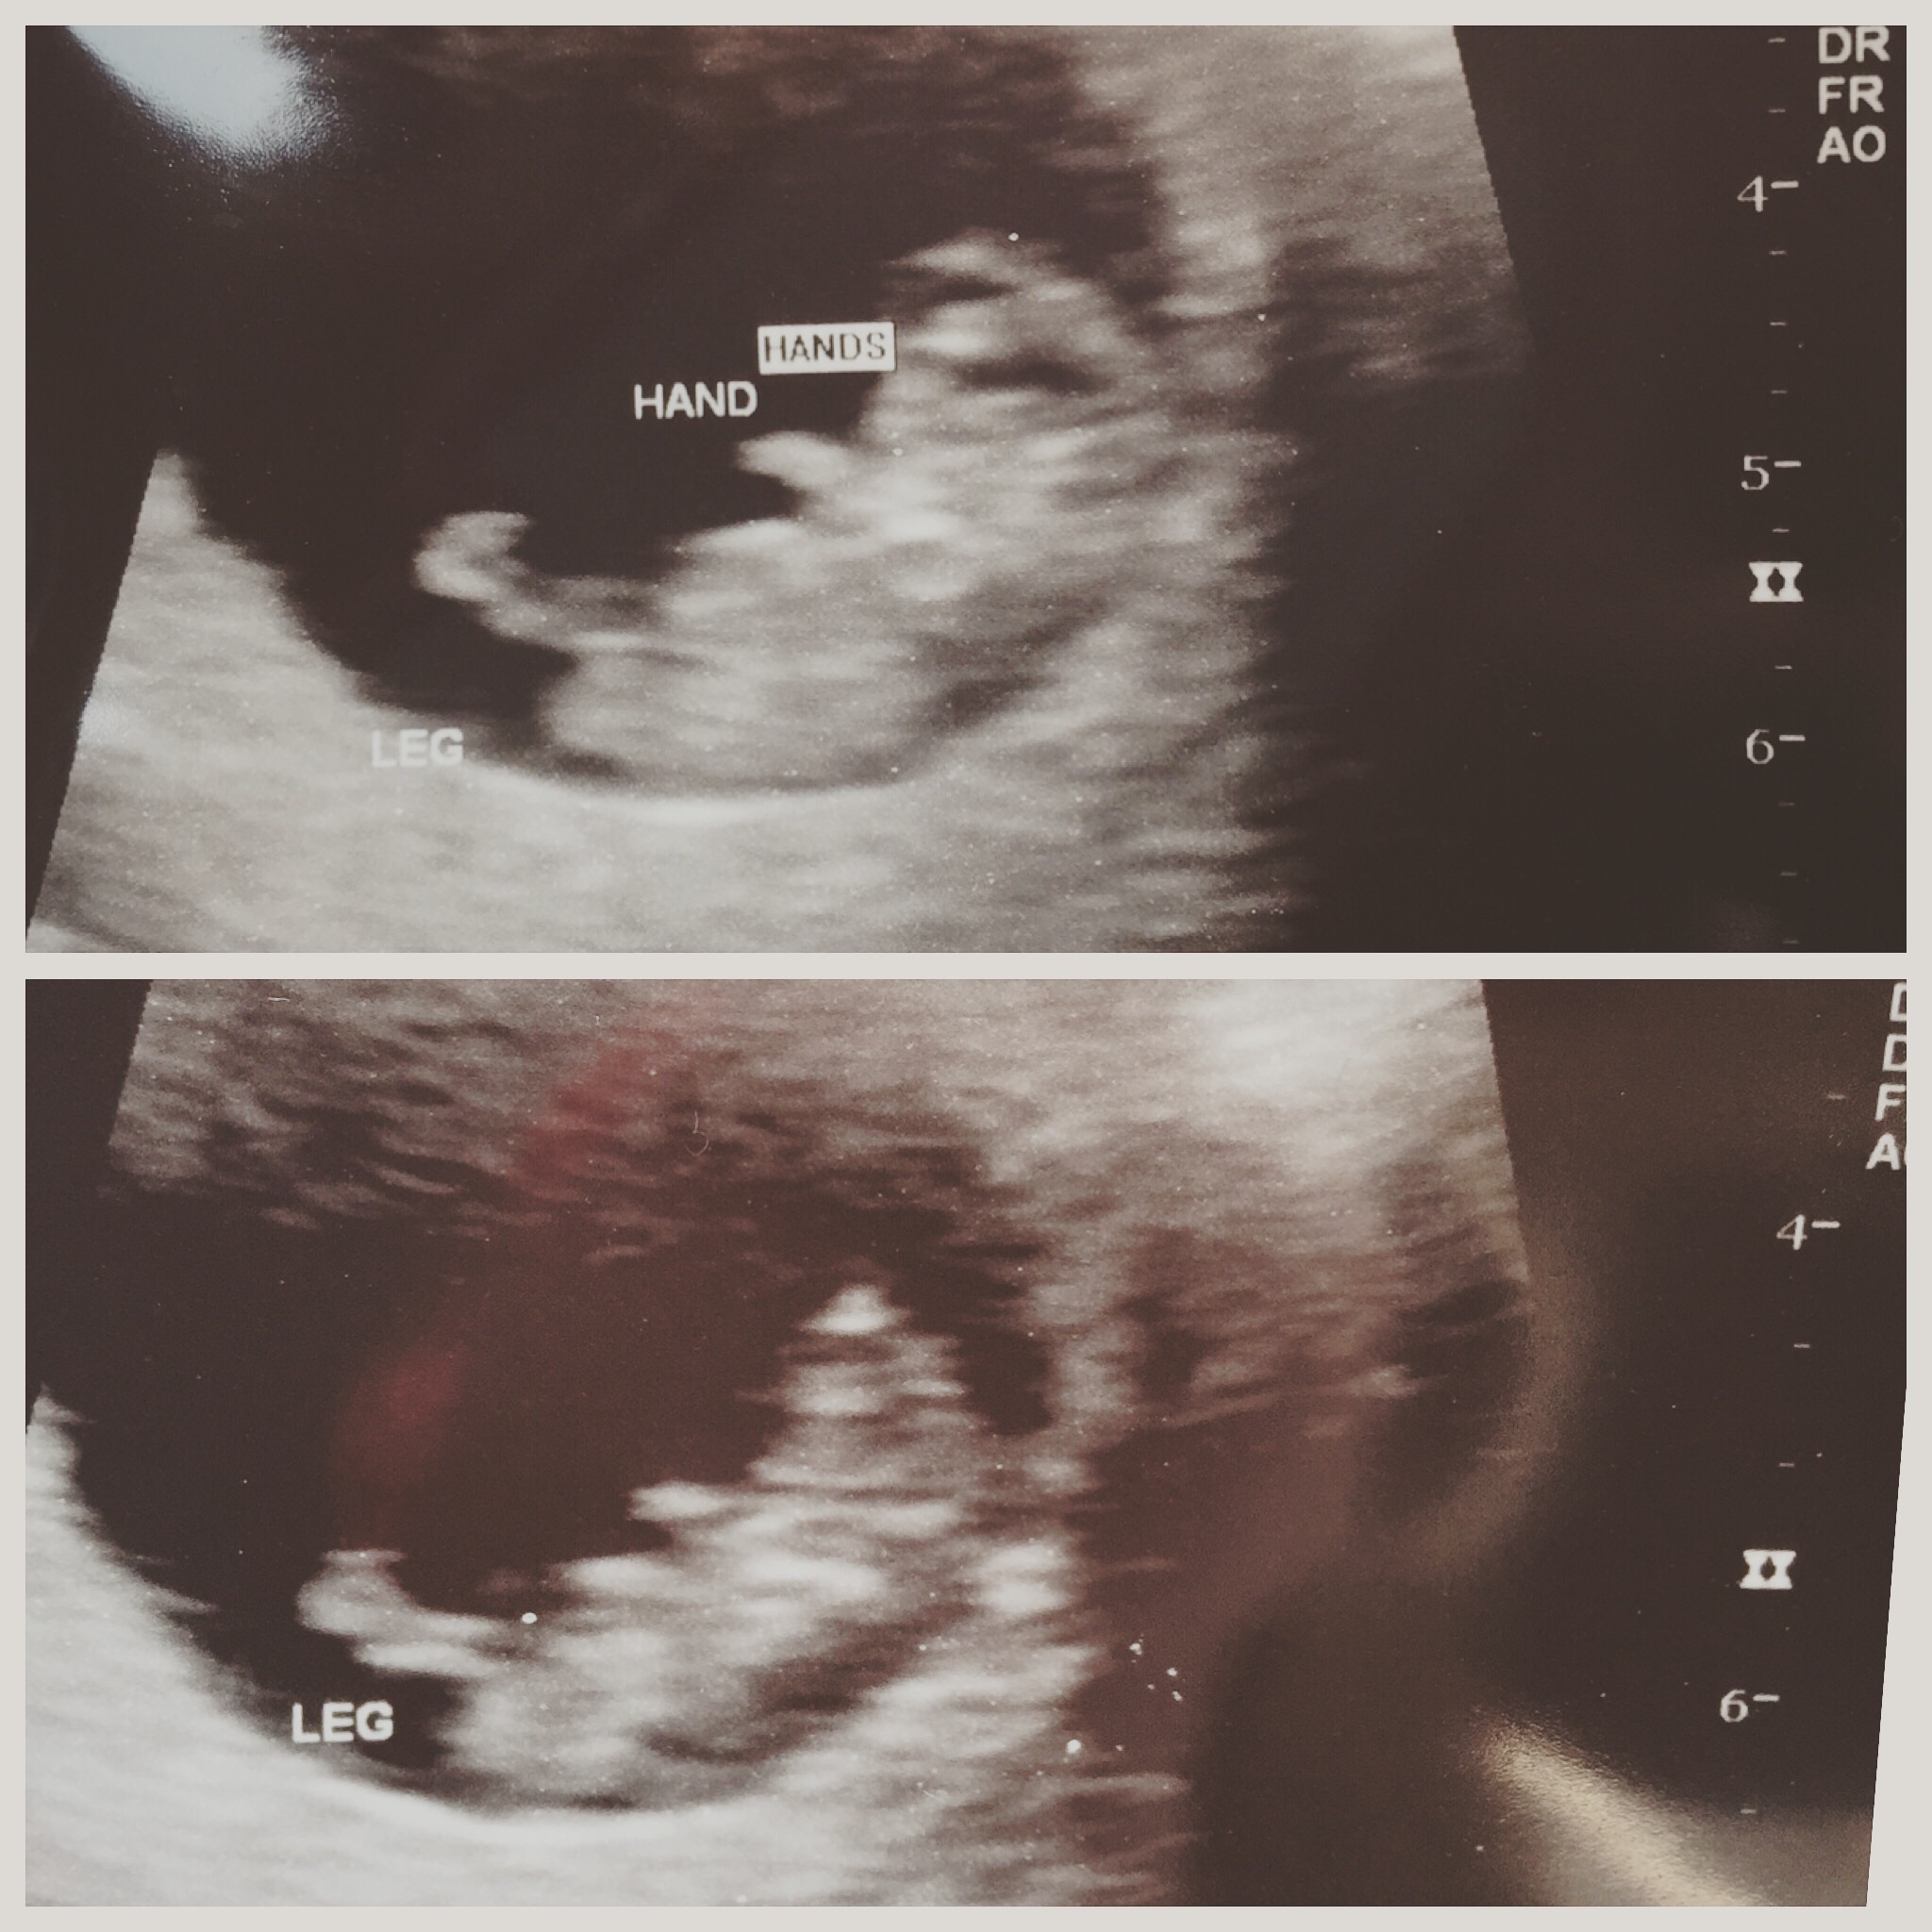

ive been so tore up and nervous over my ultrasound this morning I was almost in tears last night! Well.... Everything is PERFECT heart rate is 172 I'm measuring right on 9w6d! We got to see our baby move around and kick its little legs and even wave at us. It kept putting its hand up to its face

I'm so blessed, that's was the sweetest most heart melting noise I've ever heard I couldn't be any happier. I cried when I heard it and seen how much baby has grown! No one could wipe the smile off my face or my boyfriends. (Baby didn't get long legs from its momma! Must be from daddy!)

We even saw it dance a bit on the US.. Such an amazing experience!